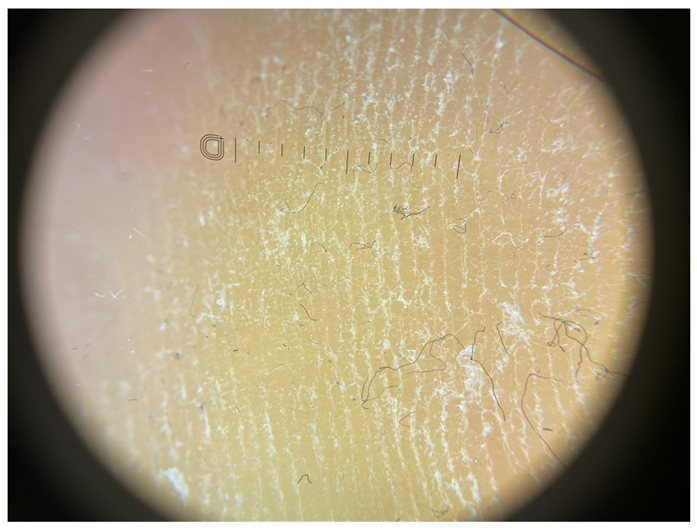

| Grade IV | Foto Finder dermatoscopy, cross-polarization |

![]() | |

| DL-5 dermatoscopy, cross-polarization | |

| DL-5 dermatoscopy, parallel polarization | |